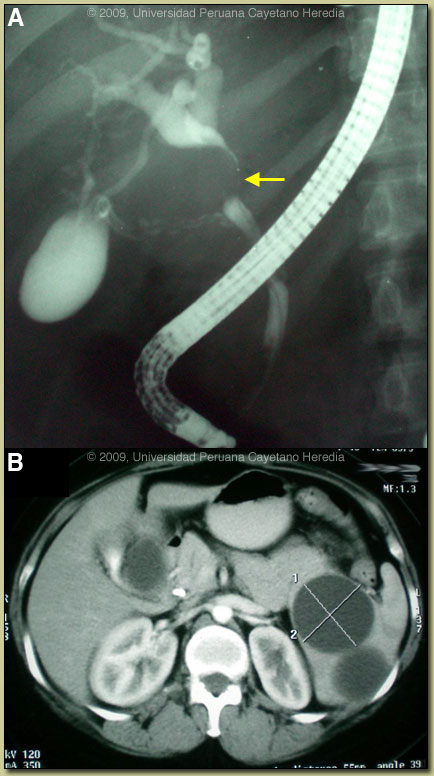

| Diagnosis: Splenic and extrahepatic hydatidosis due to Echinococcus granulosus. |

Discussion: A western blot was strongly positive for E. granulosus. Review of the CT disclosed displacement of the gallbladder due to a 3 cm cystic lesion that appeared to be extrahepatic and which at the same time appeared to be compressing the common bile duct [Image C]. Six cystic lesions within the spleen were observed [Image D]. In Perú, this is a very unusual presentation of hydatid disease with extrinsic compression of the CBD by a cyst causing cholestatis. No evidence of primary sclerosing cholangitis or cholangiocarcinoma was found during imaging or during later laparatomy (see below).